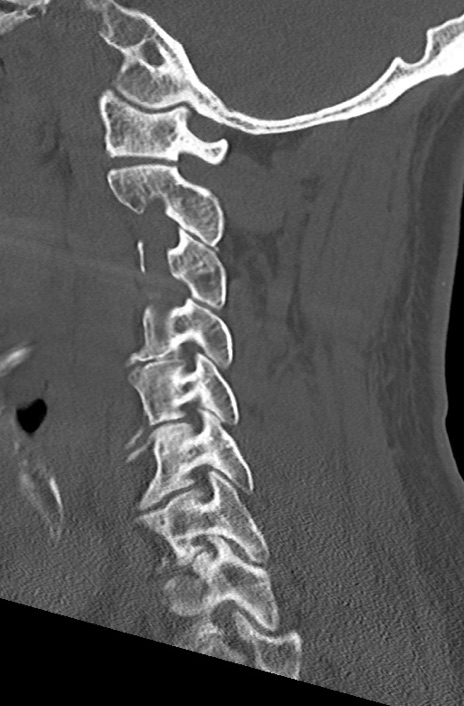

【整形】TIPS症例7 頚椎CT(矢状断像)

頚椎CT